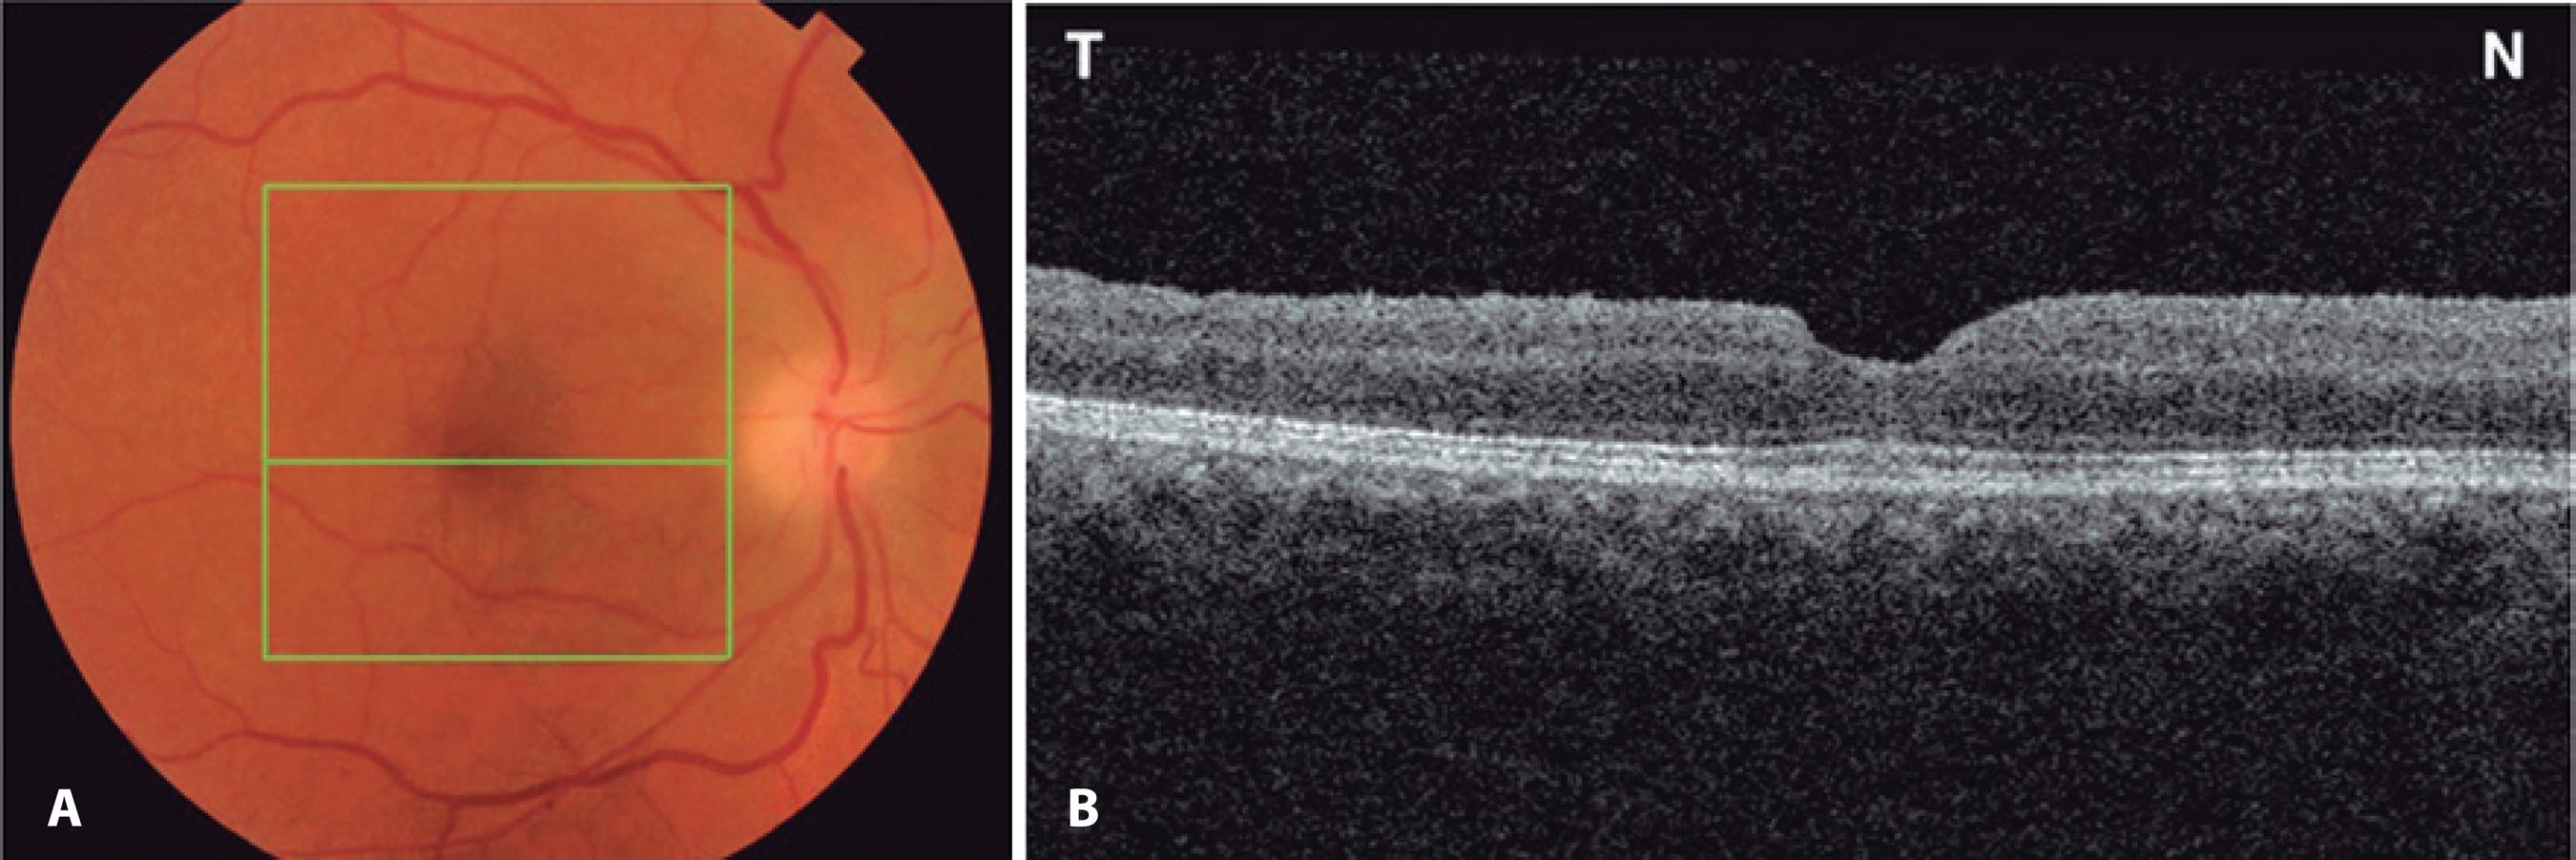

The initial postoperative VA was 20/400, with an IOP of 10 mmHg in the operative eye. On the fifth postoperative day, the patient noticed sudden painless vision loss, with the VA reduced to finger counting at 1 meter in OD. On examination, she had a right relative afferent pupillary defect with an IOP of 29 mmHg in OD. Her right optic nerve was edematous (Figure 2 A). OCT imaging of the macular area revealed macular hole closure (Figure 2 B). Automated perimetry was obtained on the 14th post-operative day and demonstrated a diffuse reduction of sensitivity with an inferior altitudinal defect (Figure 3). The erythrocyte sedimentation rate (ESR) was 20 mm/h, C-reactive protein (CRP) was <0.3 mg/l, and the patient denied any symptoms suggestive of giant cell arteritis (GCA). A fixed combination of timolol maleate 0.5% and brimonidine tartrate 0.2% (Combigan®) twice daily for OD was initiated in combination with 80 mg of prednisone orally for 7 days with subsequent dose tapering. Three months later, the best-corrected visual acuity was 20/160-1O D. The right optic nerve was pale, and the macular hole remained closed (Figure 4).

Figure 2 A) Fundus retinography demonstrating optic disc edema affecting the right eye 7 days after surgery. B) Fundus retinography of same eye. C) Optical coherence tomography (horizontal scan) demonstrating complete closure of the macular hole.